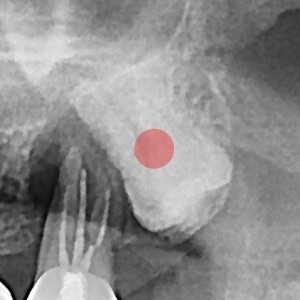

사랑니발치 완전 매복 사랑니

98c9148a81c37bd910ebd0e3dd27d654_1764727368_5811.jpg